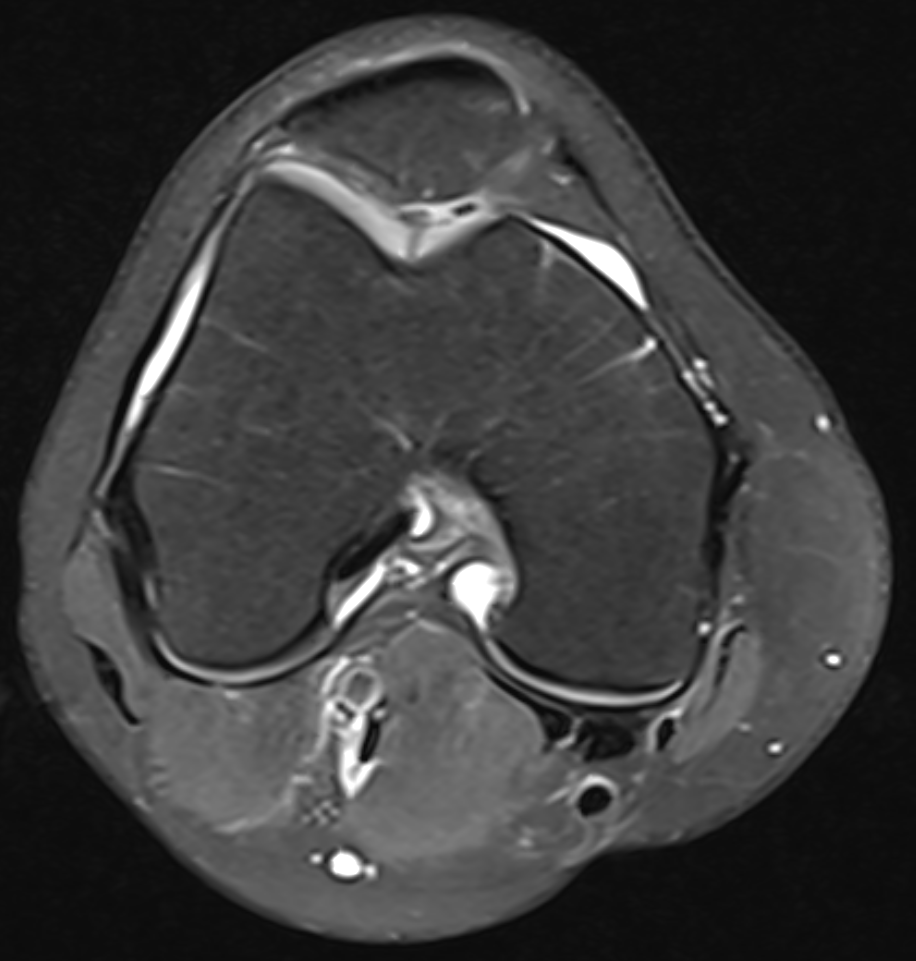

3. Black PD cartilage sign - chondrocalcinosis in chondral fissure